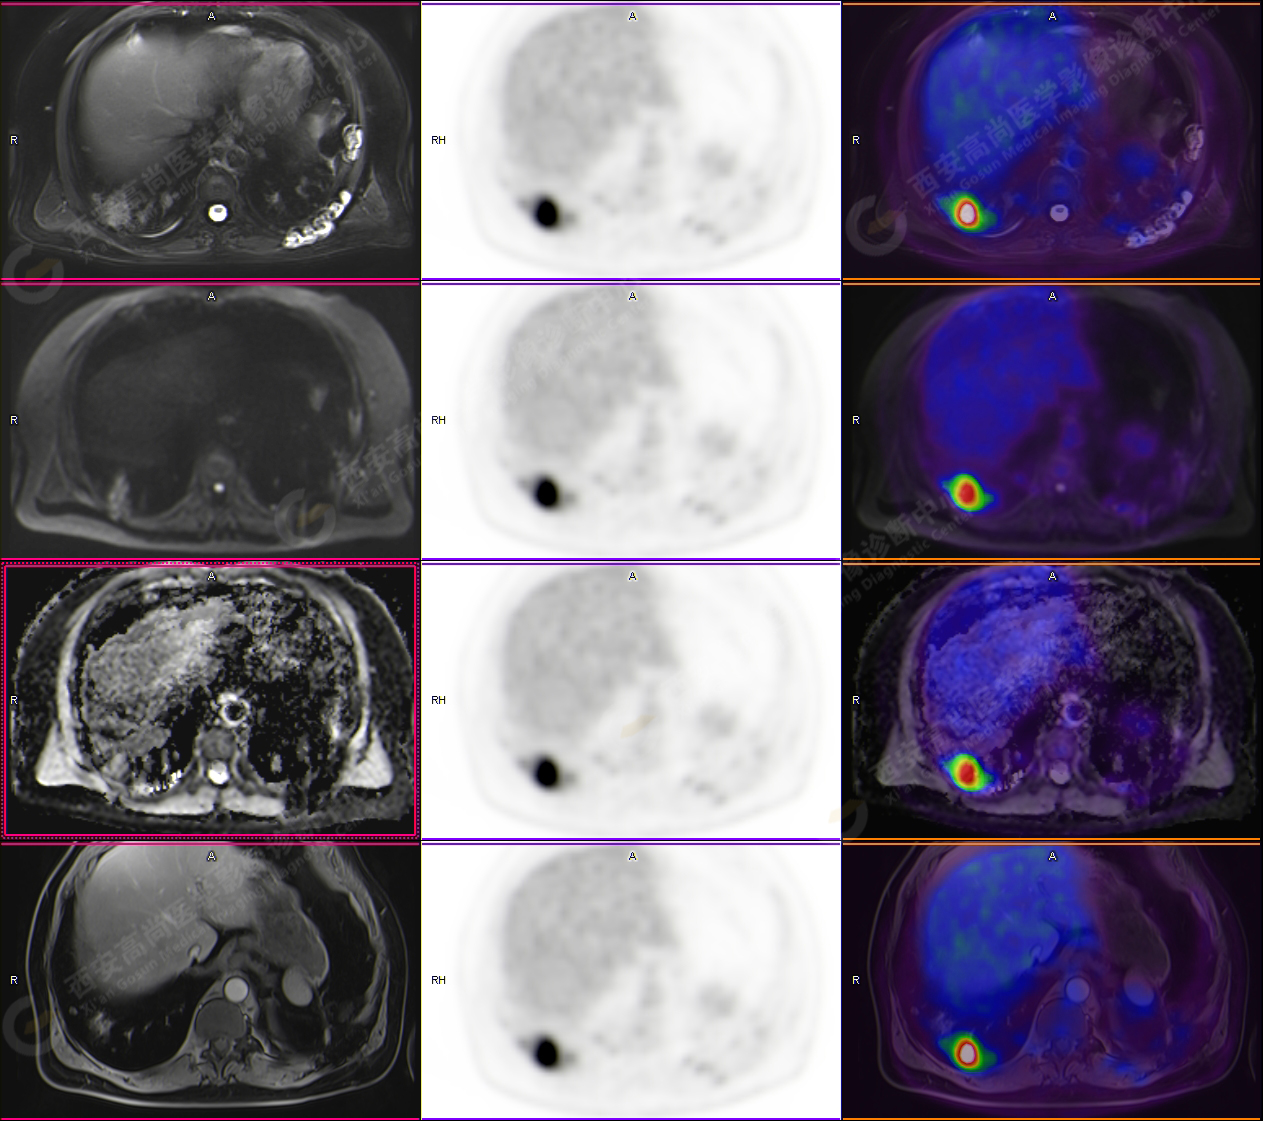

男性,53歲,頭暈半月入院,CT發(fā)現(xiàn)肺內(nèi)腫塊,雙肺多發(fā)大小不等實(shí)性及粟粒樣結(jié)節(jié),雙肺門(mén)及縱隔多發(fā)腫大淋巴結(jié)。病程中無(wú)發(fā)熱、胸悶氣及胸部不適。既往:左側(cè)肋骨外傷史。

PET-MR圖像